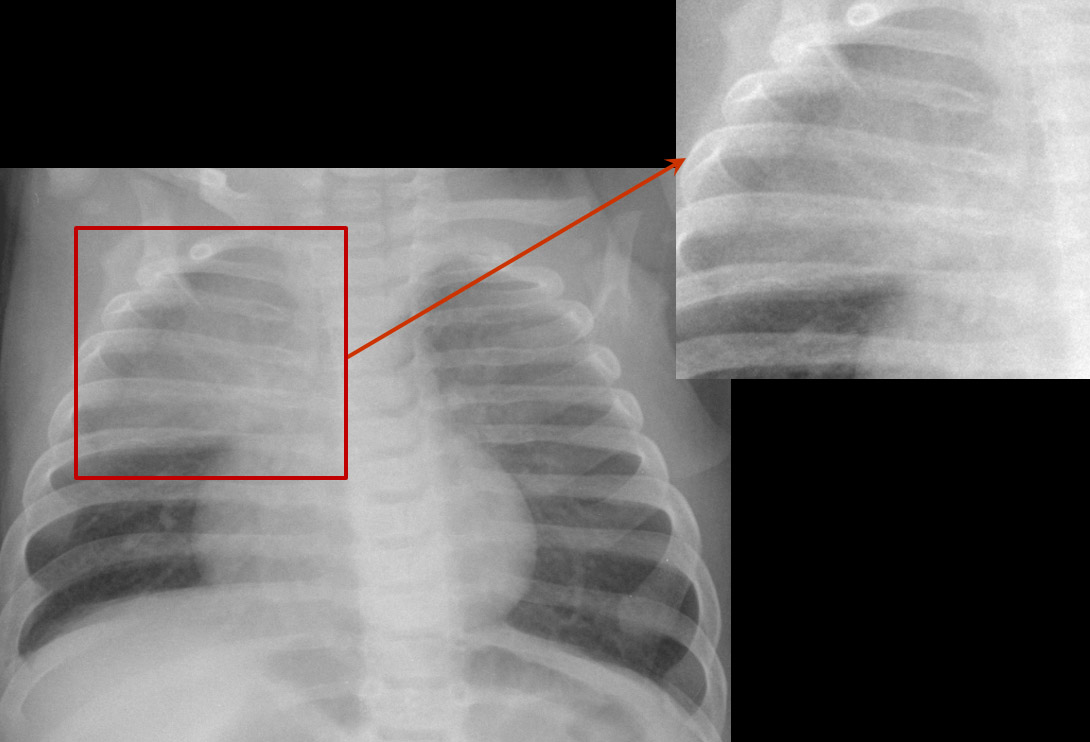

El timo es una glándula mediastínica anterior que forma parte del sistema inmune. En el neonato presenta un tamaño grande en proporción al tórax, y no se suele identificar en radiografías de mayores de 2-3 años. En condiciones normales se presenta en la radiografía como una masa de densidad agua que no comprime la vía aérea ni los grandes vasos, pues es de consistencia blanda y se adapta a las estructuras vecinas.

• Signo de la vela tímica: forma triangular unilateral.

• Signo de la oleada: contorno suavemente festoneado por la impronta de los arcos costales anteriores.